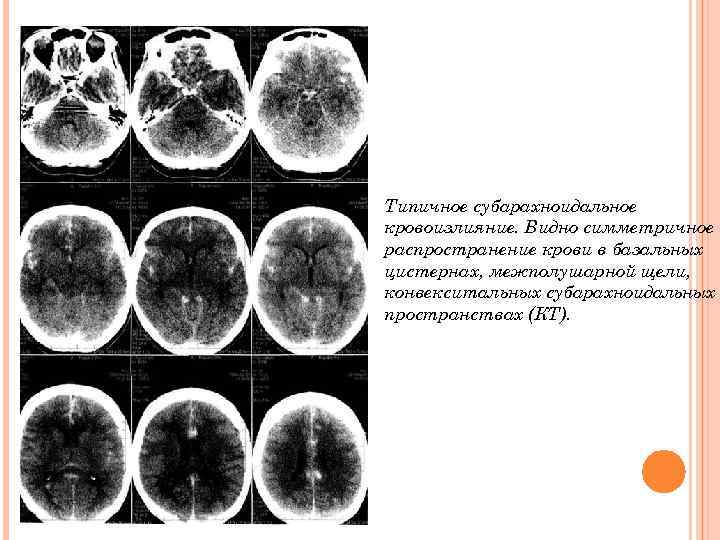

Типичное субарахноидальное кровоизлияние. Видно симметричное распространение крови в базальных цистернах, межполушарной щели, конвекситальных субарахноидальных пространствах (КТ).